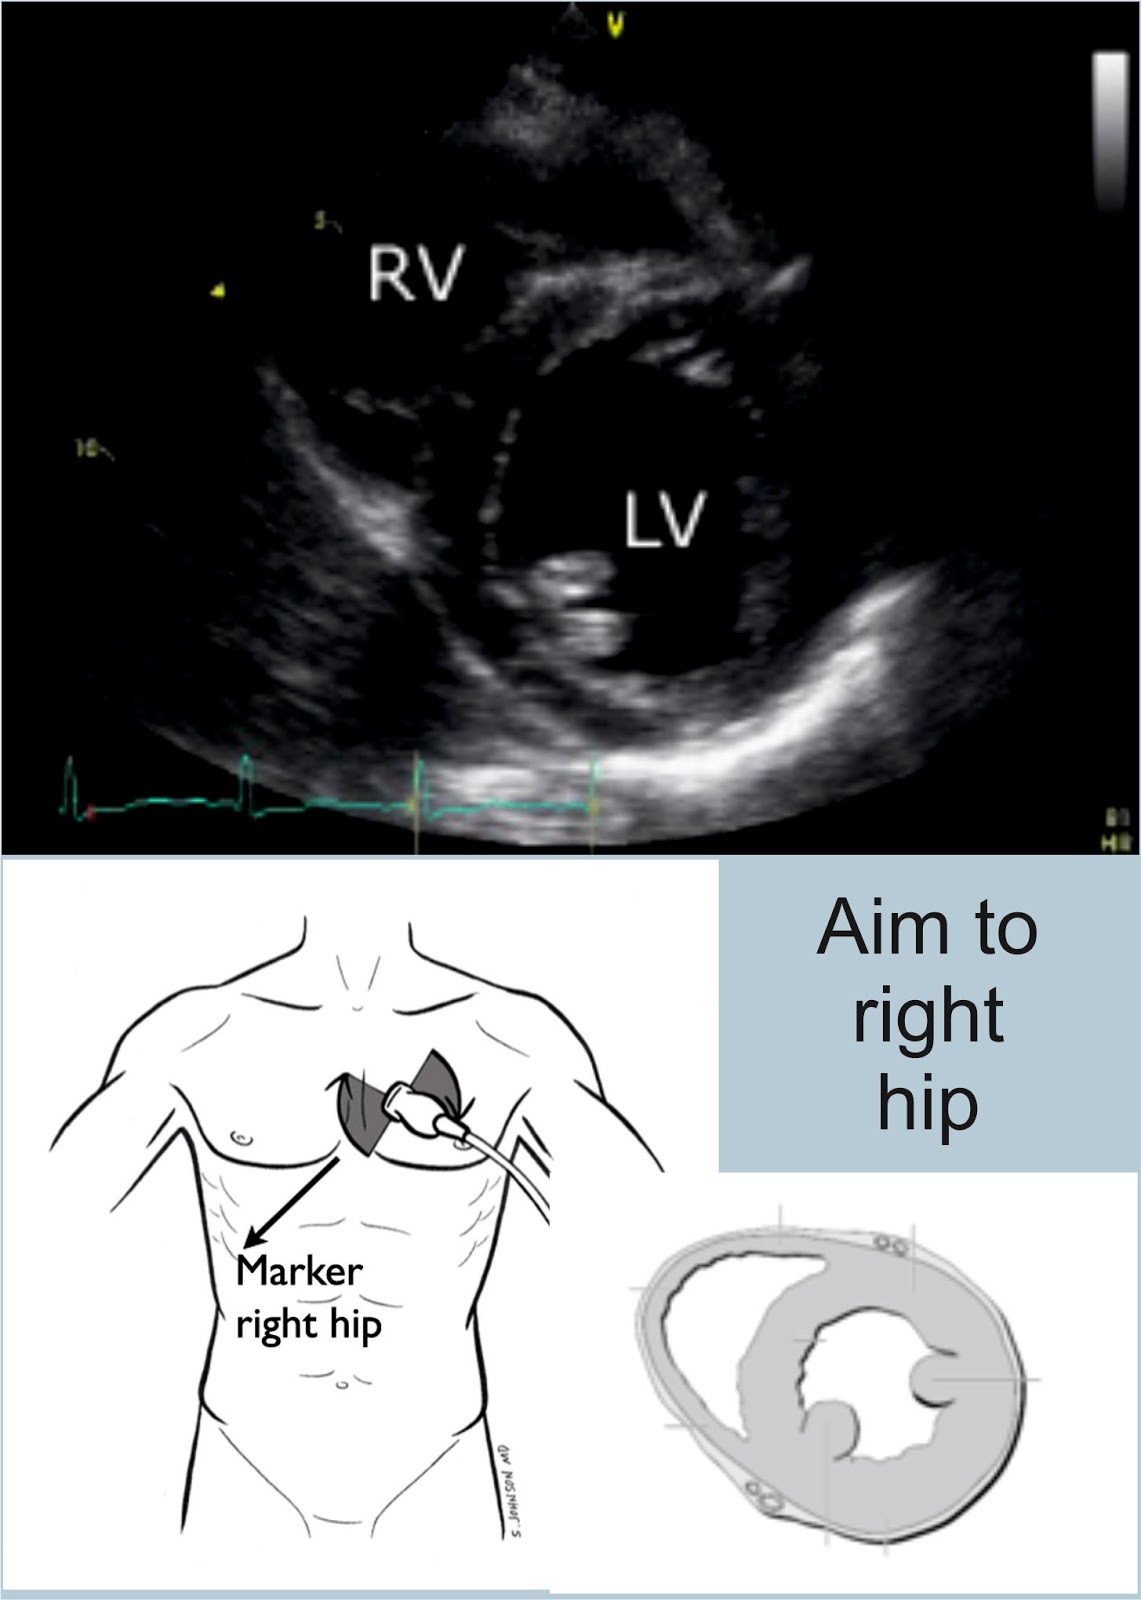

Subxiphoid or Subcostal View

Because the heart is tilted slightly, the probe hits the liver first, then the right hand side of the heart, and then the left hand side - hence the view you get with the right side of the heart at the top, and the left at the bottom.

- Look at LV RV (?dilated)

Rotate the probe to look at the patient's left shoulder, keeping the probe marker on the patient's left. This gives you a view at the bottom of the heart - looking at the ventricles.

If you scan at the level of the mitral valve, you get the croissant and doughnut appearance. You also get the fish mouth. This is the view we are aiming to get.